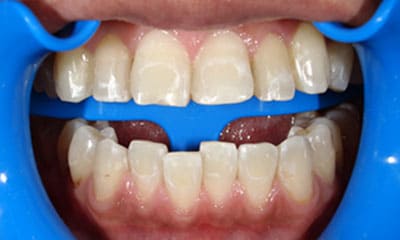

● 歯根が折れ保存不可の歯を抜歯して、そのスペースに八重歯を並べた症例

藤沢デンタルオフィスの虫歯や破折で抜歯後の部分矯正